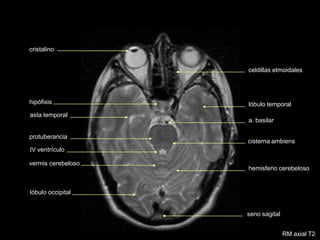

cristalino

celdillas etmoidales

tallo hipofisario

nervio óptico

cist.supraselar

cist. interpenduncular

acueducto de Silvio

vermis cerebeloso

lóbulo occipital

a. cerebral media

RM axial T1 con contraste